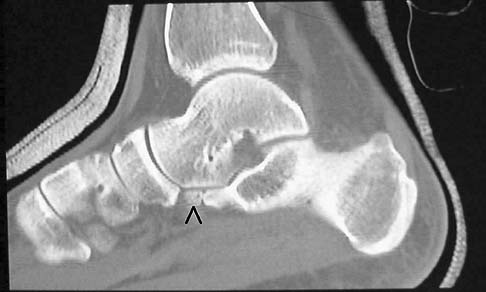

Calcaneus Fractures